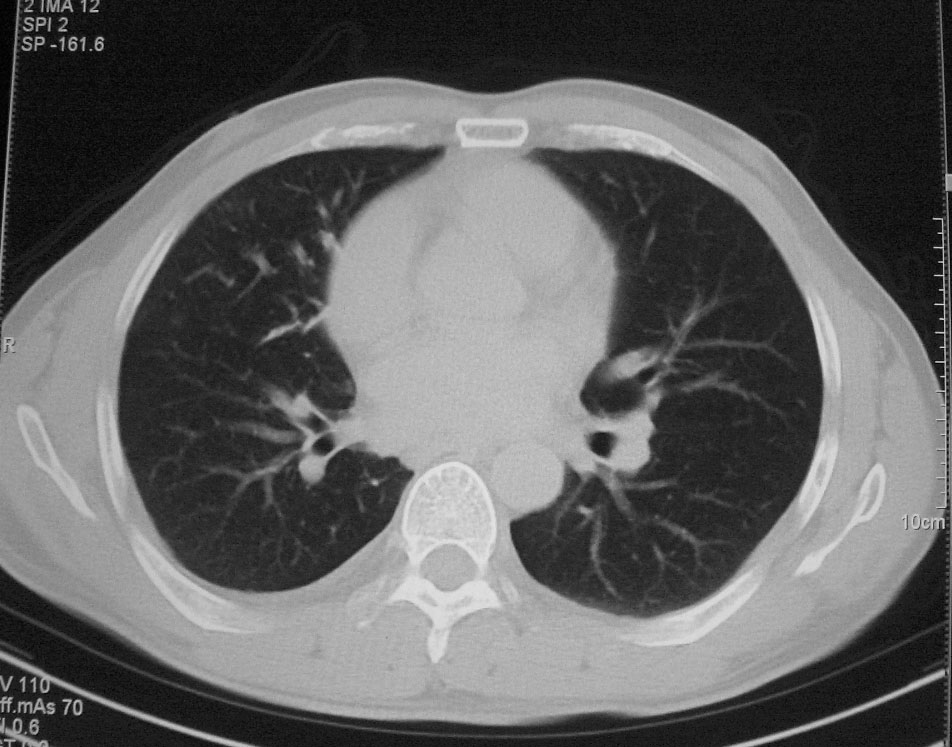

标题: CT5485:[原创]肺部占位请讨论

右上肺ca并肺不张,纵隔淋巴结转移

右肺上叶中央型肺癌并上叶肺不张、纵隔淋巴结肿大

右上叶支气管后壁明显增厚,支持右肺上叶中央型肺癌伴右上叶肺不张、纵隔淋巴结肿大。

左肺上叶不张,可见软组织肿块,左肺上叶支气管狭窄,呈鼠尾征,左侧胸腔内见少许积液,纵隔内未见肿大淋巴结,建义做个增强或支气管镜

右上叶支气管后壁明显增厚,支持右肺上叶中央型肺癌伴右上叶肺不张、纵隔淋巴结肿大。建议支气管镜检查。

右上肺中央性肺癌伴右侧胸腔少量积液!右上肺胸膜下还有一小病灶,不完全排除结核,但个人支持恶性肿瘤!建议早穿刺活检。

右上叶支气管开口变窄,纵隔见肿大的淋巴结。支持右上叶中心型肺癌并右上叶不张纵隔淋巴结肿大。

右肺上叶中央型肺癌并上叶肺不张、纵隔淋巴结肿大.右侧少量胸腔积液。